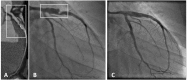

Coronary artery aneurysms (CAAs) are uncommon and describe a localized dilatation of a coronary artery segment more than 1.5-fold compared with adjacent normal segments. The incidence of CAAs varies from 0.3 to 5.3%. Ever since the dawn of the interventional era, CAAs have been increasingly diagnosed on coronary angiography. Causative factors include atherosclerosis, Takayasu arteritis, congenital disorders, Kawasaki disease (KD), and percutaneous coronary intervention. The natural history of CAAs remains unclear; however, several recent studies have postulated the underlying molecular mechanisms of CAAs, and genome-wide association studies have revealed several genetic predispositions to CAA. Controversies persist regarding the management of CAAs, and emerging findings support the importance of an early diagnosis in patients predisposed to CAAs, such as in children with KD. This review aims to summarize the present knowledge of CAAs and collate the recent advances regarding the epidemiology, etiology, pathophysiology, diagnosis, and treatment of this disease.